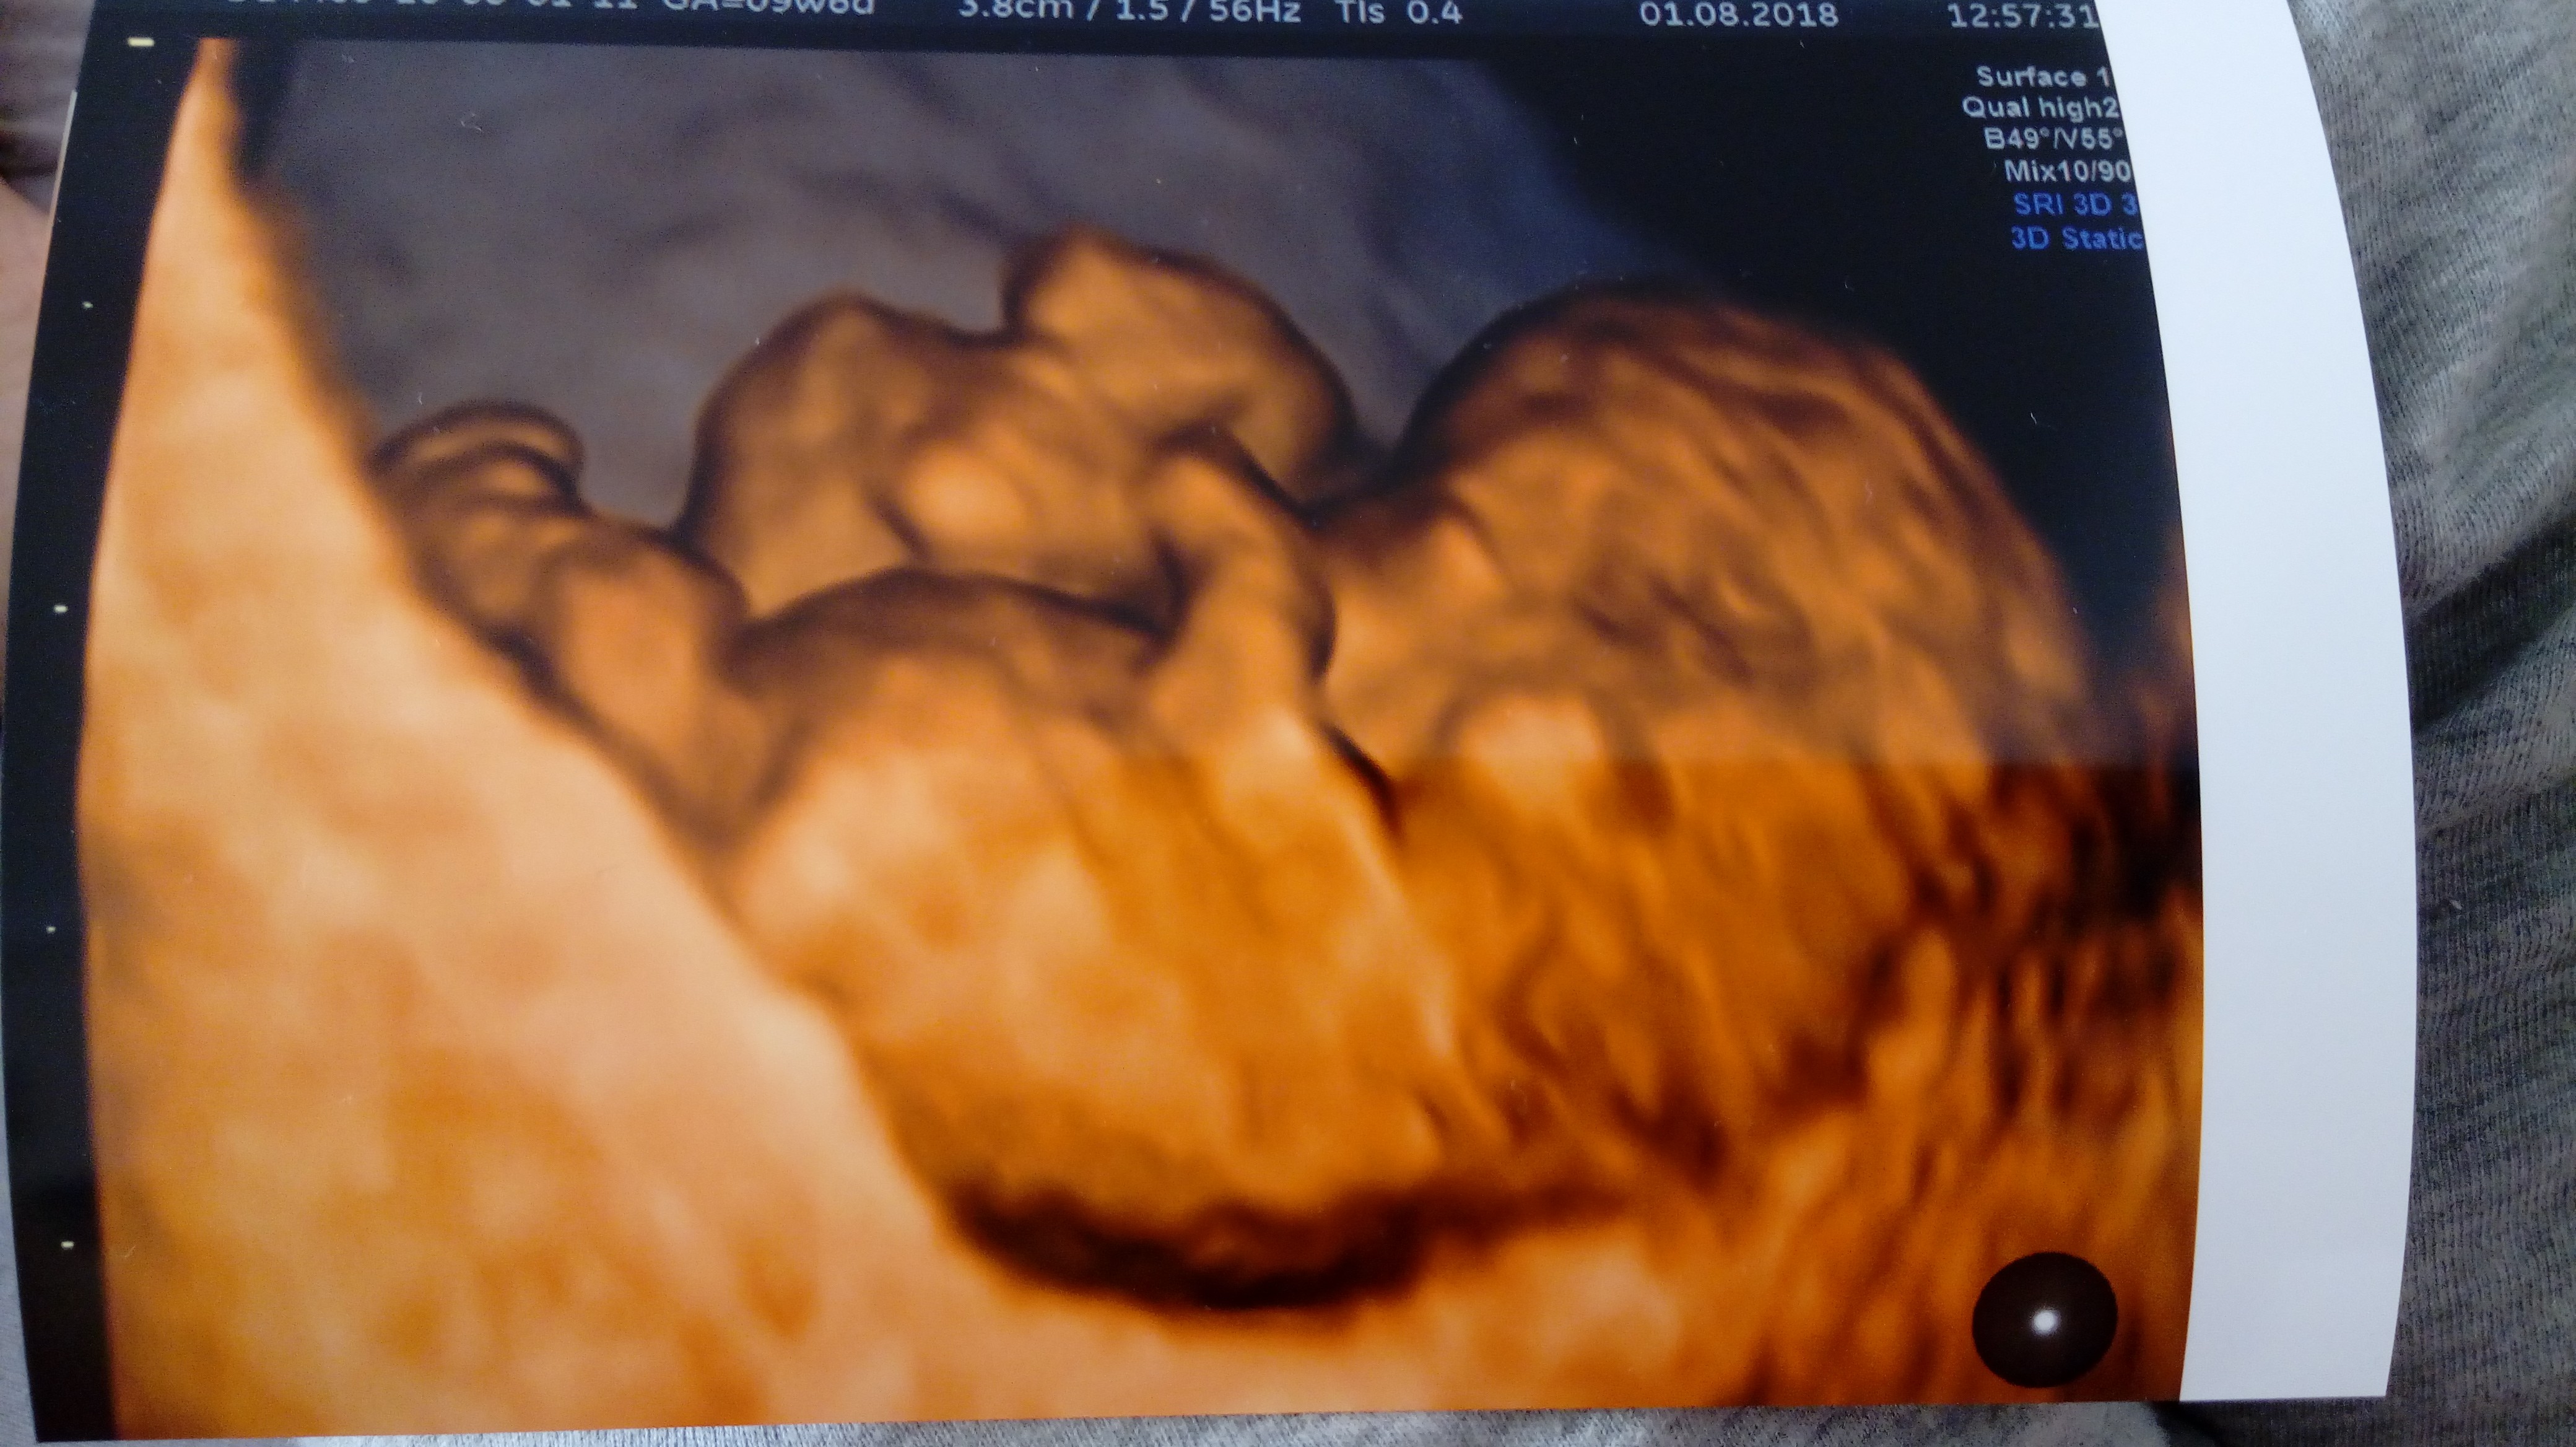

Jestem w 10tc, to moja trzecia ciąża dodam że nie planowana a czwarte dziecko;) Termin mam na koniec lutego początek marca ale czuję że będzie to marzec:biggrin2: A to moja kruszynka

Zobacz załącznik 884575